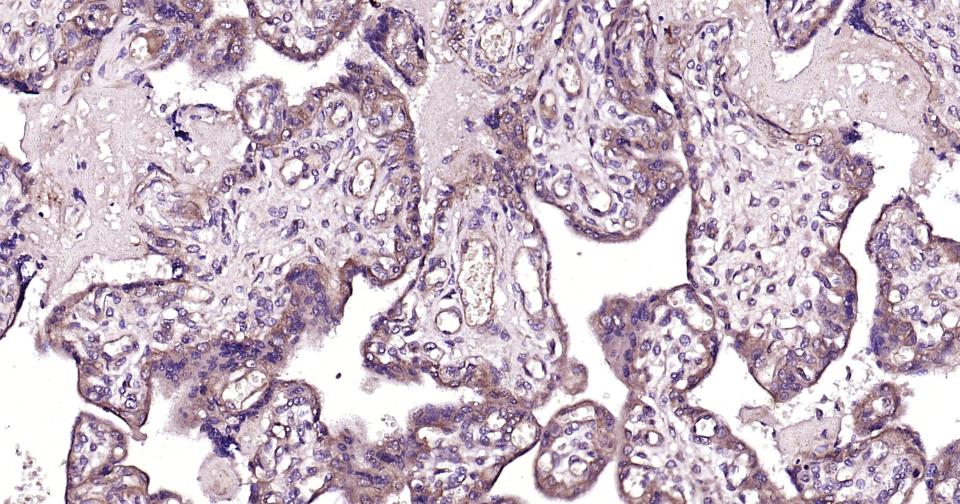

Paraformaldehyde-fixed, paraffin embedded Human Placenta; Antigen retrieval by boiling in sodium citrate buffer (pH6.0) for 15 min; Antibody incubation with Phospho-TBK1 (Ser172) Polyclonal Antibody, Unconjugated (bs-3440R) at 1:200 overnight at 4°C, followed by conjugation to the SP Kit (Rabbit, SP-0023) and DAB (C-0010) staining.